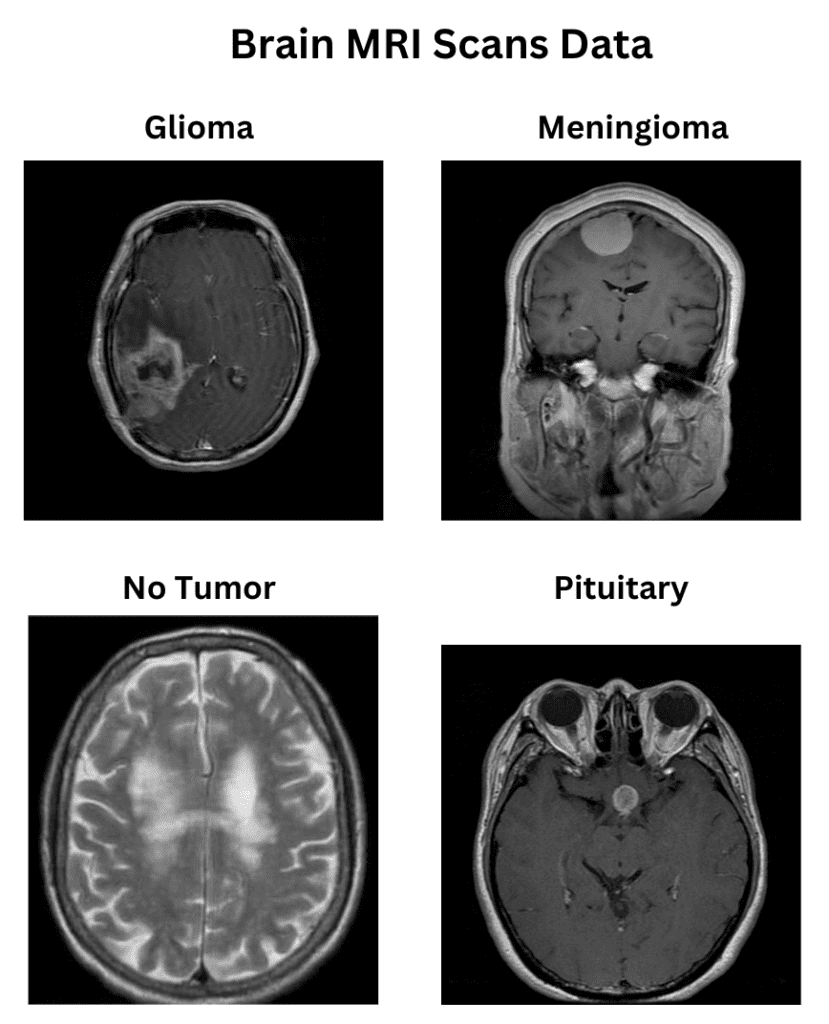

The Brain MRI Scan Data for Brain Tumor Classification

The dataset consists of 1311 Brain MRI scans, primarily curated for brain tumor classification. The dataset deals explicitly with four categories of brain tumors, namely:

- Glioma (300 samples)

- Meningioma (306 samples)

- No tumor (405 samples)

- Pituitary (300 samples)

The dataset is more or less balanced, with a slight excess of non-tumor sample instances.